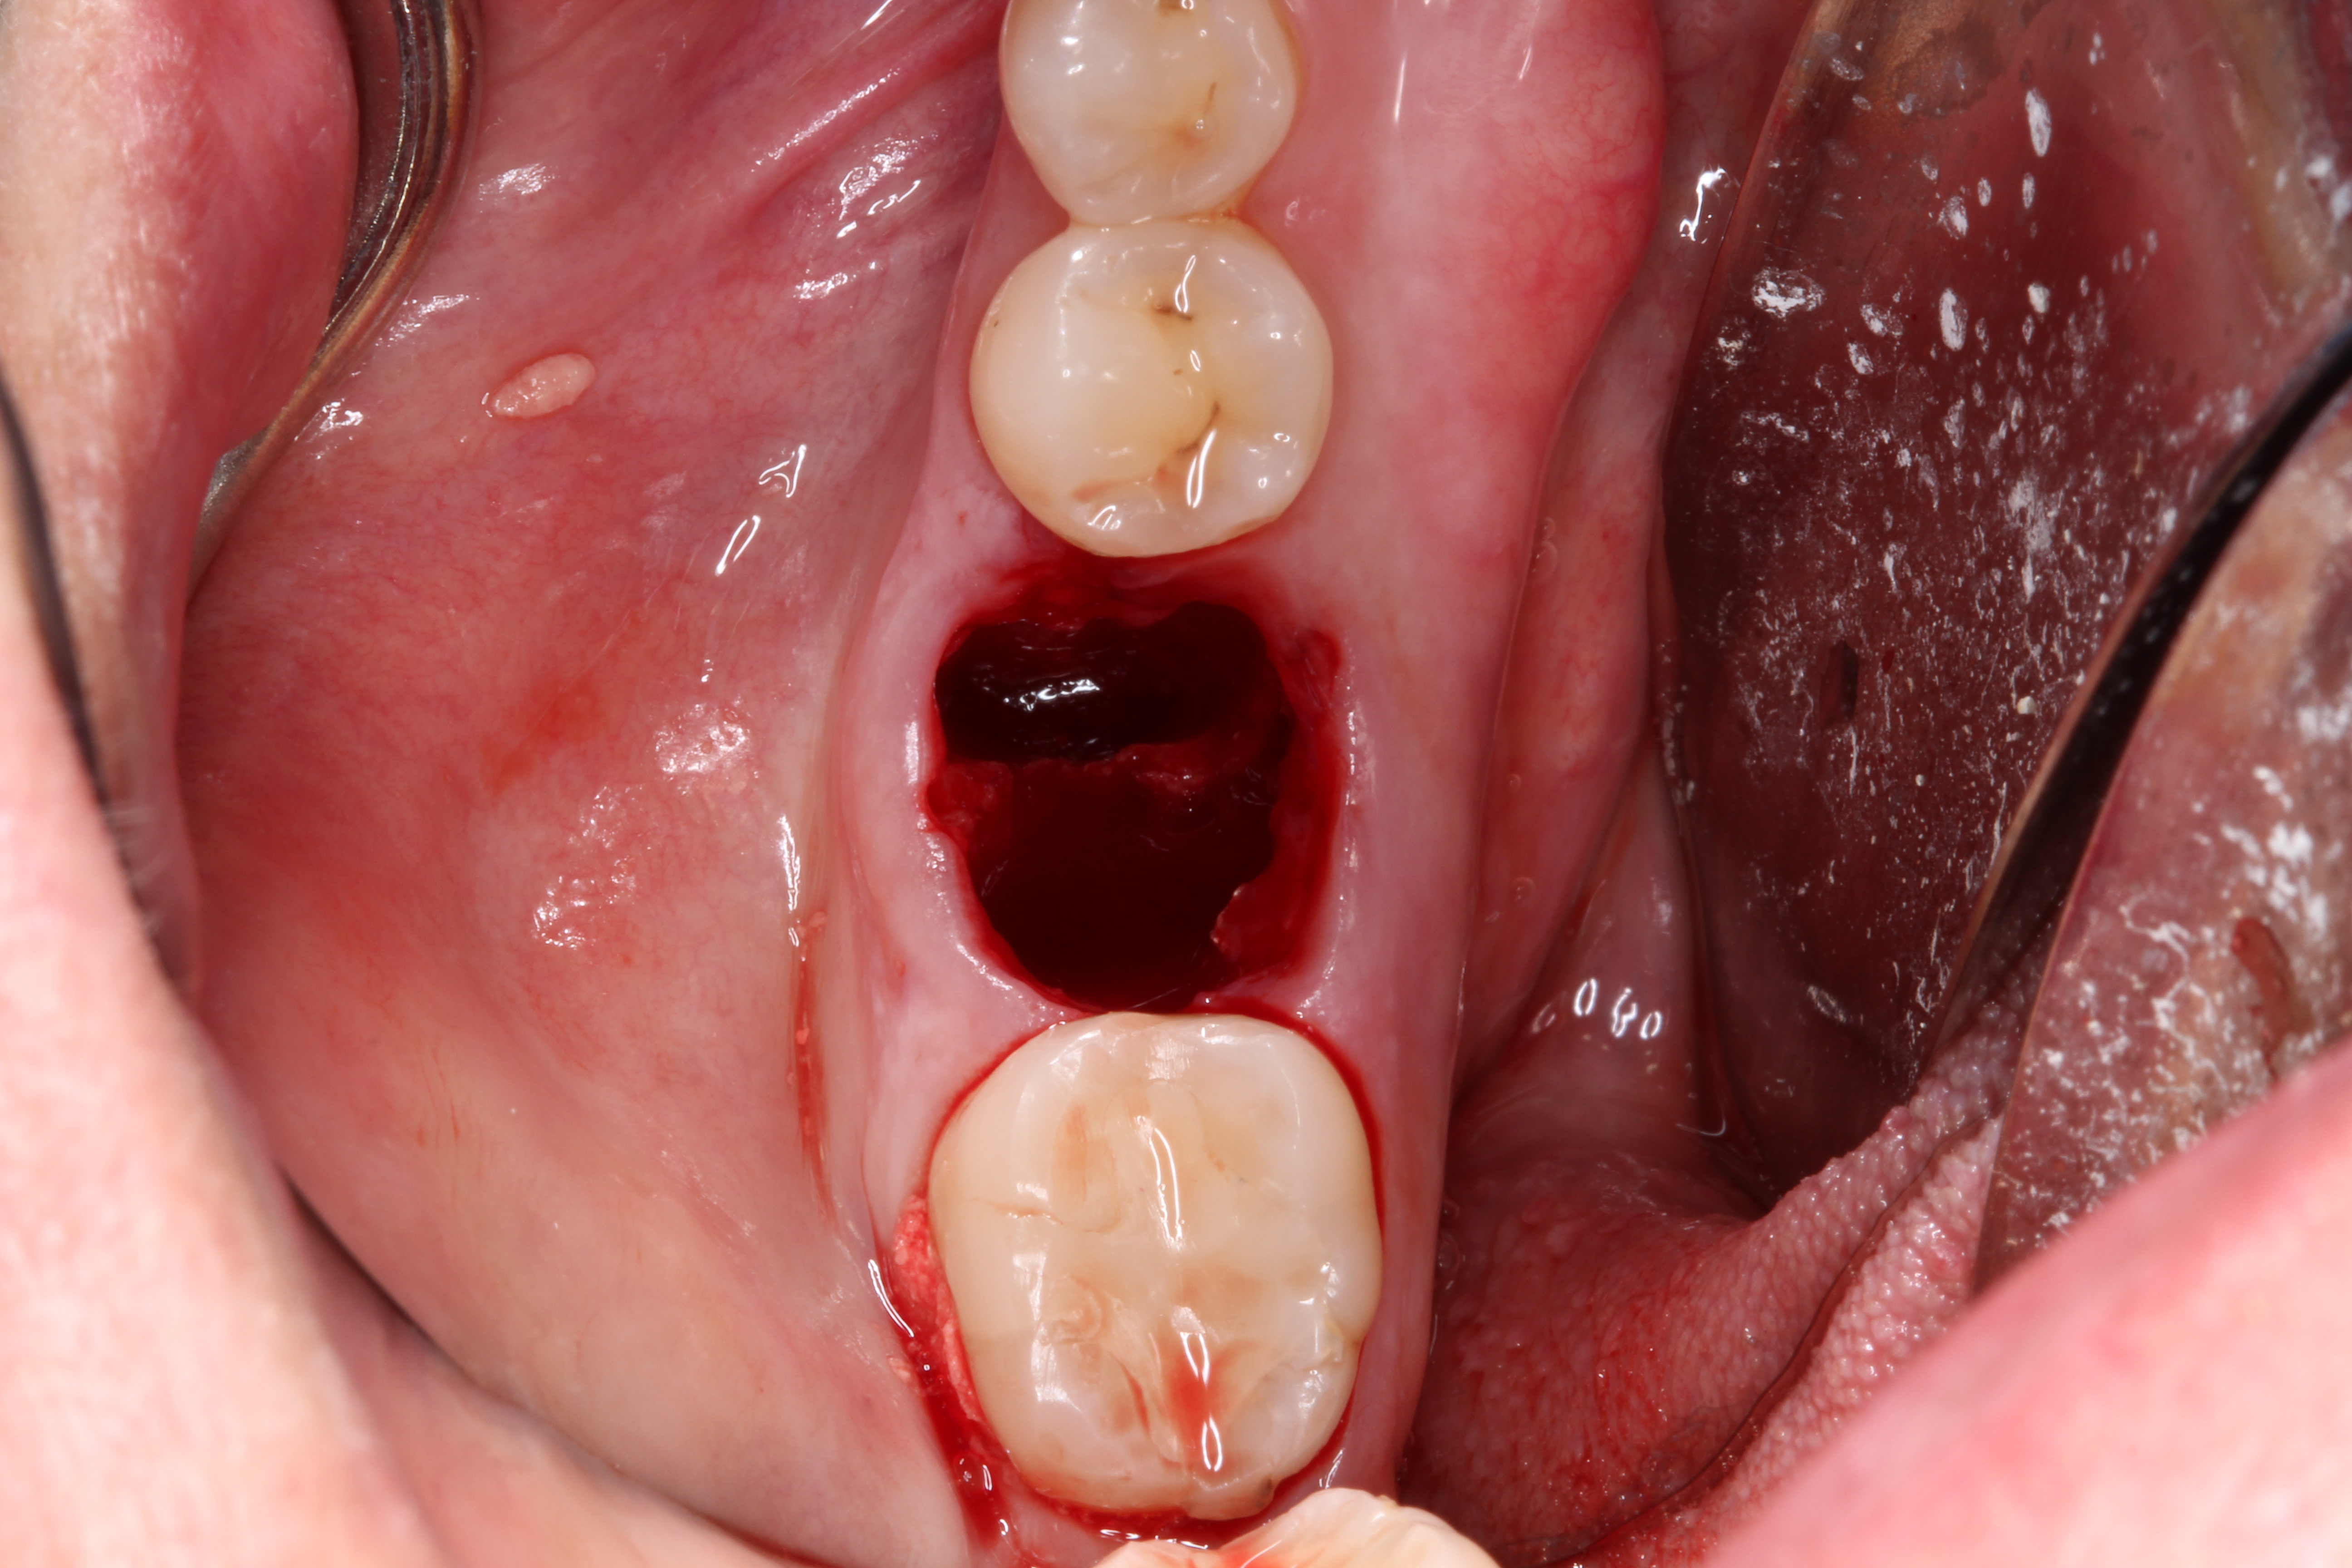

Fig 6.The socket must be bleeding before delivering the graft material. This facilitates the healing cascade and greatly increases the success of the socket preservation.

Figure 6

3. Make sure the socket is bleeding (Figure 6). If necessary, decorticate the remaining socket walls, using a round bur or surgical-type bur, to create a bleeding wound that will facilitate early vascularization and the beginning of the primary healing cascade.